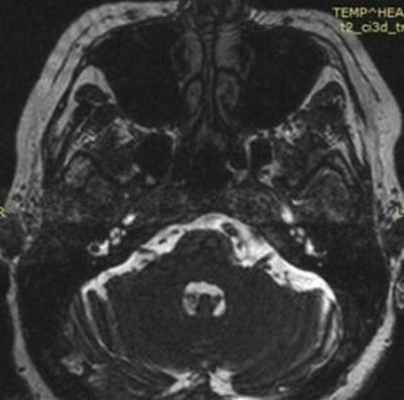

На аксиальной и сагиттальной томограммах четко визуализируется правый тройничный нерв и прилегающая к его верхнему контуру правая верхняя мозжечковая артерия

(Слева) При аксиальном исходном изображении (МРА) у пациента с спазмом правой половины лица визуализируются извитая правая позвоночная артерия и ЗНМА, воздействующие на область выхода корешка лицевого нерва. В цистерне мостомозжечкового угла (ММУ) визуализируется лицевой нерв.

(Справа) При аксиальной МРТ CISS на уровне цистерн ММУ у пациента с правосторонним гемифациальным спазмом определяется петля ЗНМА, смещающая ЧН VII в цистерне ММУ кзади, в результате чего он «свешивается» с заднего края слухового отверстия.

(Слева) При аксиальной МРТ CISS у пациента с левосторонним гемифациальным спазмом визуализируется петля левой позвоночной артерии, выдающаяся в цистерну ММУ, где она воздействует на проксимальную часть лицевого нерва в области выхода корешка.

(Справа) При аксиальной МРТ Т2 ВИ у пациента с гемифациальным спазмом определяется долихоэктазия позвоночной артерии, воздействующей на зону выхода корешка лицевого нерва во внутренних отделах цистерны ММУ. Приблизительно у 50% пациентов с гемифациальным спазмом обнаруживаются изменения на МРТ, обычно на тонкосрезовых Т2 последовательностях или МРА.

Рис. 1. МРТ головного мозга в аксиальной и коронарной проекциях: отмечается близкое расположение петли базилярной, петли ветви верхней мозжечковой и передней нижней мозжечковой артерий к корешку левого лицевого нерва в зоне его выхода из вещества моста.